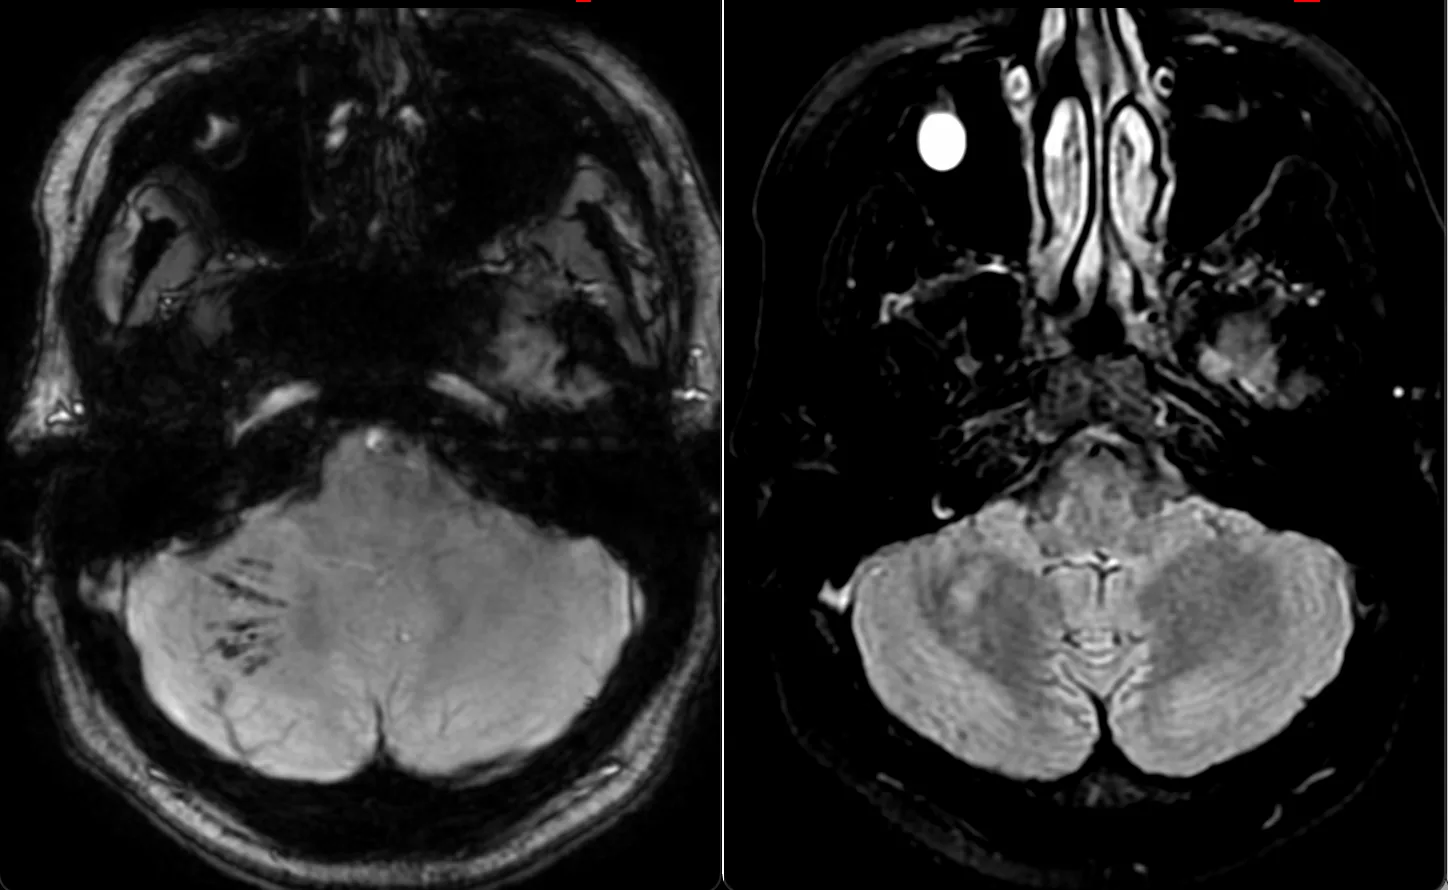

Мужчина 35 лет, месяц назад упал с высоты двух метров, сейчас не полностью ориентирован в месте и времени. Типичная (кроме мозжечка справа) картина травматического аксонального повреждения 3 степени (с поражением ствола). Множественные мелкие точечные и линейные микрокровоизлияния, вокруг части из них видны глиоз/отек. А вот в мозжечке, реально, нечасто такое увидишь. Но бывает. Типа, как вот здесь: